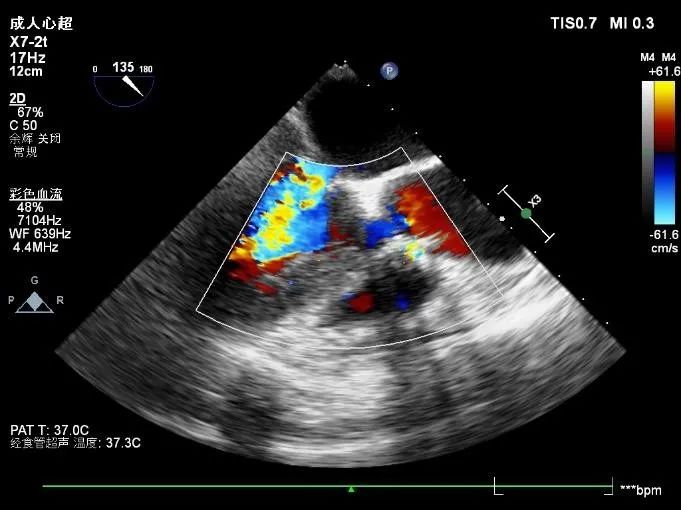

患者女性,72岁,主诉胸闷、气短,以“心力衰竭”入院,超声检查主动脉瓣Vmax=4.88m/s,PGmean=58mmHg,主动脉瓣返流彩束面积1.0cm³,诊断为重度主动脉瓣狭窄伴少量反流。

超声评估:

跨瓣压差:

术前跨瓣压差86mmHg

术后跨瓣压差7mmHg